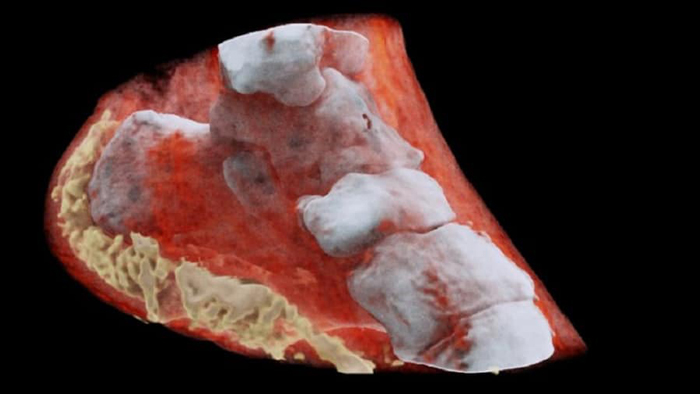

বিশ্বের প্রথম রঙিন এক্স-রে

মানুষের শরীরে এই প্রথম রঙিন ও থ্রিডি এক্স-রে করলেন নিউজিল্যান্ডের বিজ্ঞানীরা। এ কাজে তারা এমন এক প্রযুক্তি ব্যবহার করেছেন, যা রোগ শনাক্তকরণে উন্নতি আনবে। এ প্রযুক্তি সরবরাহ করে ইউরোপিয়ান অর্গানাইজেশন ফর রিসার্চ বা সংক্ষেপে সার্ন।

বিবৃতিতে সার্ন এর দাবি, এই রঙিন এক্স-রে প্রযুক্তিতে আরও স্পষ্ট ও পরিষ্কার ছবি পাওয়া যাবে। যা ডাক্তারদের রোগ নির্ধারণে বিশেষ সহযোগিতা করবে।

সার্নের এই প্রযুক্তিকে বলা হচ্ছে মেডিপিক্স। এটি একটি ক্যামেরার মতো কাজ করছে। এটি প্রত্যেকটি আণবিক কণাকে শনাক্ত ও গুনতে পারছে। যখন শাটার খোলা হচ্ছে, তখন কণা ও পিক্সেলগুলো একে অপরের সঙ্গে ধাক্কা খাচ্ছে। এতে যে ছবি উঠছে তা হাই রেজুলেশন ও হাই কন্ট্রাস্টের।

সার্ন জানিয়েছে, এই পদ্ধতিতে তোলা ছবিতে খুব সহজেই হাড়, পেশি ও কার্টিলেজকে পৃথক করা যাচ্ছে। সঠিকভাবে জানা যায়, ক্যান্সার আক্রান্ত টিউমারের আকার ও অবস্থান।